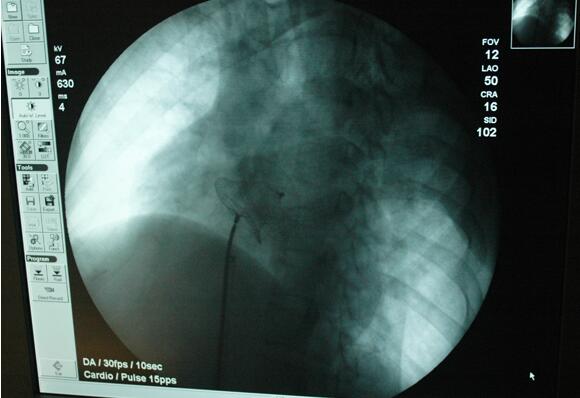

环江东兴莫女士,今年28岁,近1个月以来,在上楼、爬坡时反复出现胸闷、气紧等现象,休息后仅略有好转,由于病情反复,先后经多家医院治疗但病情没有好转。于11月30日前来我院就诊,经过我院心血管内科专家的细心检查,心脏听诊有明显杂音。后经过心脏彩色B超检查,提示为先天性心脏病、动脉导管未闭(管型,左向右分流),被诊断为先天性心脏病,在主动脉及肺动脉之间存在一条异常通道,若不及时治疗会出现心脏扩大、心衰、肺动脉高压等症状,一旦出现右向左分流即失去手术机会,患者会很快出现心衰加重死亡。在病情紧急的情况下,我院心血管内科医护人员对患者病情进行讨论,决定实施心脏病封堵术。12月8日,患者被推进心导管室,医护人员在大型C臂机的引导下,仅在患者大腿部位处穿刺一个针眼,通过导管、导丝进入体内达心脏病变部位主动脉及肺动脉之间异常通道进行封堵,术中采用心脏彩色B超机直接监测封堵情况及封堵后有无渗漏现象,易于控制封堵器的释放和回收,经过不到1小时的紧张手术,吴某主动脉及肺动脉之间异常道得到根治,手术获得成功。